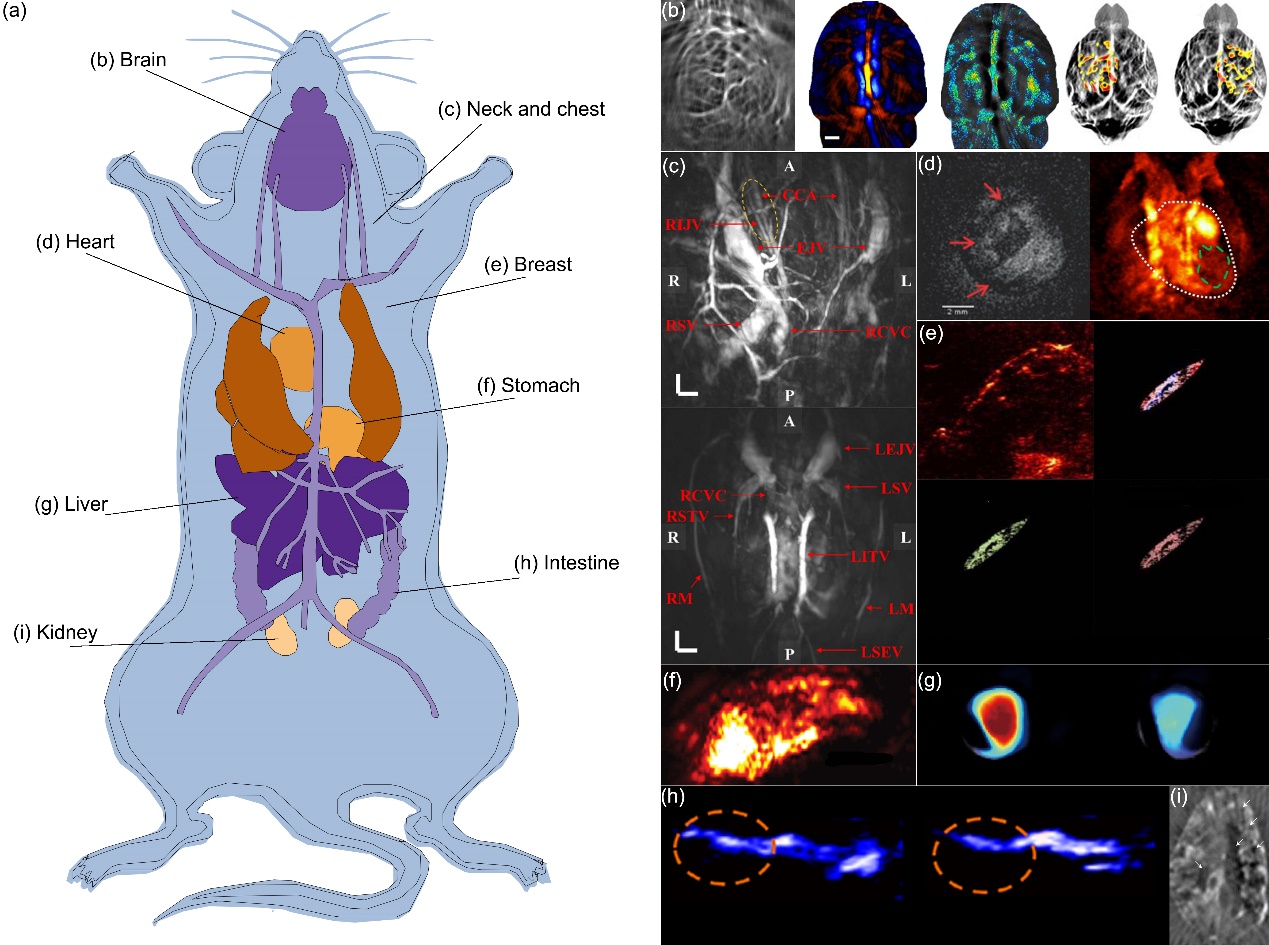

图1小鼠PACT成像

最近,PACT在临床前和临床实践中受到越来越多的关注。到目前为止,已经出现了越来越多为特定的生物医学成像应用而设计的PACT系统,实现了从小动物(图1)到人体器官(图2),从体外到体内实时成像,从简单的结构成像到使用外部造影剂的功能和分子成像。因此,总结以往PACT系统在生物医学成像和临床实践中的应用是非常重要的。这篇综述中搜索了过去二十年来与生物医学组织和样本的PACT成像有关的研究;将这些研究分为两类,即动物的PACT成像和人类组织、器官的PACT成像,并讨论了这些研究的意义。最后讨论了PACT在生物医学应用中的未来方向。随着外源性造影剂的发展和成像技术的进步,未来PACT将使生物医学成像从器官到全身,从表层血管到内部器官,从解剖到功能,在生物医学研究和临床实践中发挥越来越重要的作用。